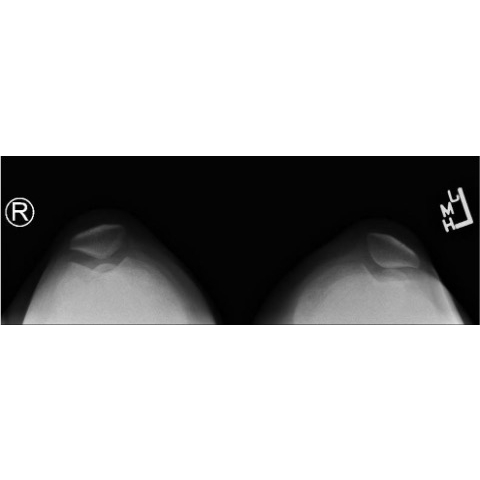

| The Kneediest Puzzle: Chronic Joint Pain With A Surprising Angle In A Young Girl - Page #3 | |||